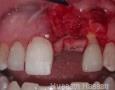

2 Months

7 Months